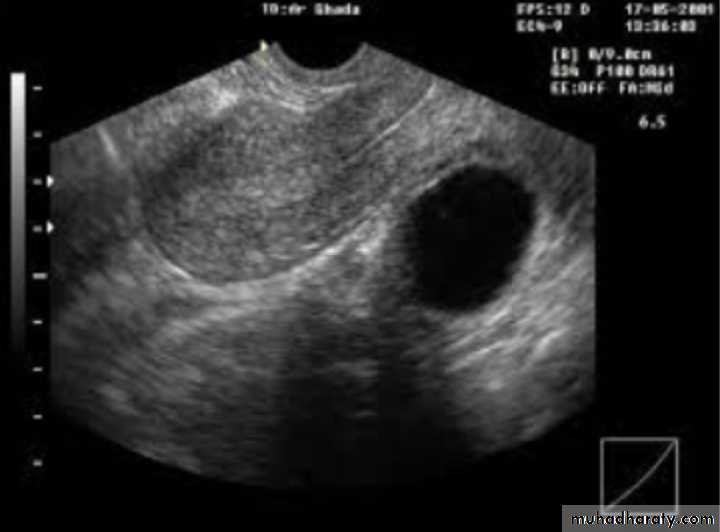

Dx: simple ovarian cyst

Description: round regular; smooth outline ;single echogenicity ;not contain blood ,contain only fluid

Tx:

-small and asymptomatic : conservative tx ;COCP

-large and symptomatic: surgical removal of cyst